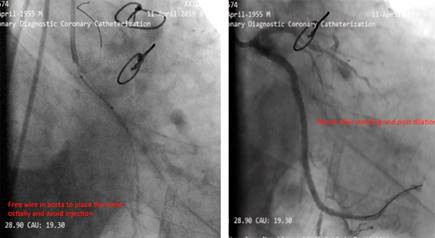

Our aim was to use the SVG as retrograde conduit for CTO PCI. During the procedure stenting was done but the stents balloon ruptured and made a huge dissection which caused a hematoma (Figure 4). As a bailout solution we decided to stent from the ostial LCx (Figure 5). To maintain a sufficient coronary perfusion, we decided to coil occlude due to Thrombolysis in Myocardial Infarction Score (TIMI) flow over 2 in this stenotic and thrombotic SVG so the competitive flow won’t affect the newly opened CTO’s long-term results. While coiling the donor SVG the coil dislodged. During the attempt to snare the dislodged coil with single loop snare, force by this device resulted in fracture in the dislodge coil and made two separated particles. One particle stayed in the descending aorta and the other went to the femoral artery. Both then were snared eventually (Figure 6).

Figure 5: Free wire in aorta to place the stent ostially and avoid injection. Result after stenting and post dilation.